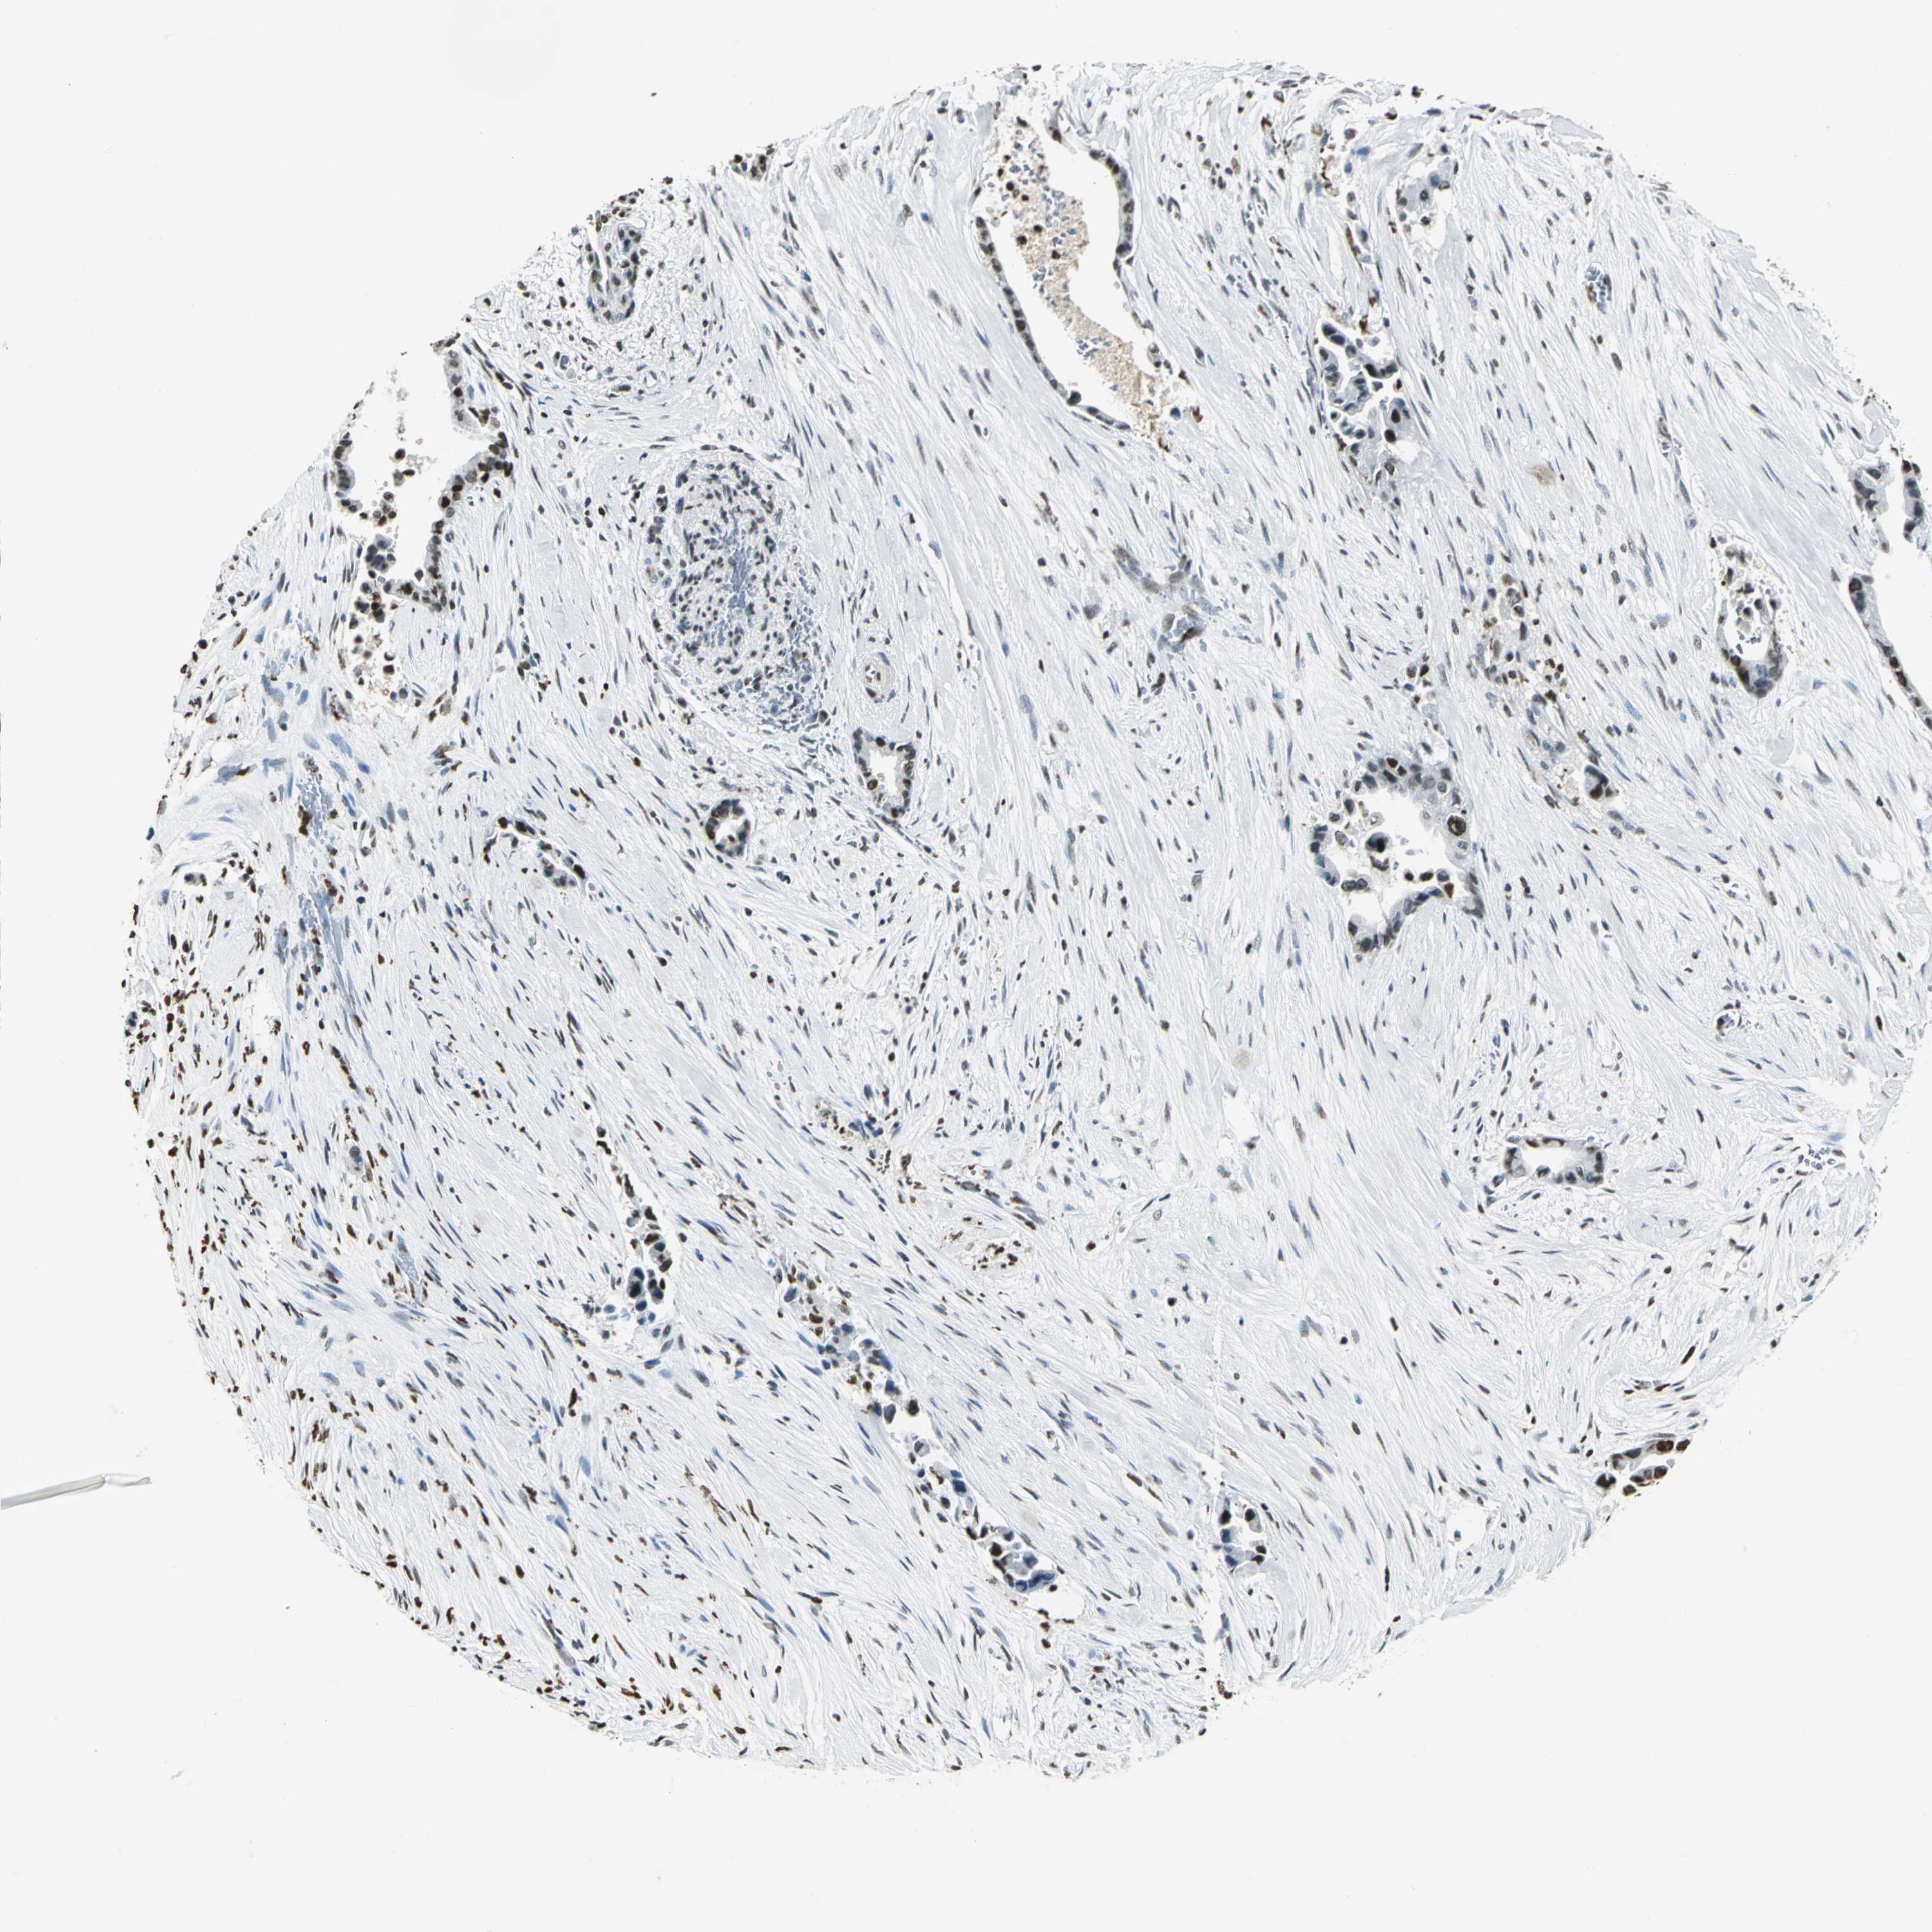

LIVER CANCER - Protein expressioni

A mouse-over function shows sample information and annotation data. Click on an image to view it in a full screen mode. Samples can be filtered based on level of antibody staining by selecting one or several of the following categories: high, medium, low and not detected. The assay and annotation is described here.

Antibody stainingi

Antibody staining in the annotated cell types in the current human tissue is reported as not detected, low, medium, or high, based on conventional immunohistochemistry profiling in selected tissues. This score is based on the combination of the staining intensity and fraction of stained cells.

Each image is clickable and will lead to virtual microscopy that enables deeper exploration of all samples and also displays staining intensity scores, fraction scores and subcellular localization as well as patient and tissue information for each sample.

Antibody HPA004873

Staining

High

Medium

Low

Not detected

Intensity

Strong

Moderate

Weak

Negative

Quantity

>75%

75%-25%

<25%

None

Location

Nuclear

Cytoplasmic/membranous

Cytoplasmic/membranous,nuclear

Cholangiocarcinoma

Carcinoma, Hepatocellular, NOS